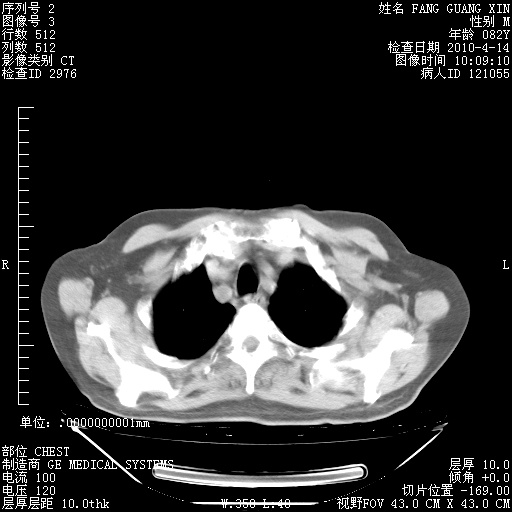

4月14日肺部CT

23.JPG

24.JPG

25.JPG

26.JPG